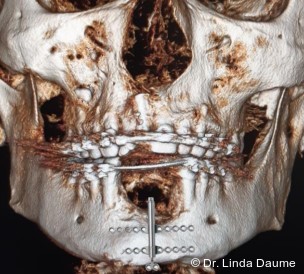

Nach umfassender Aufklärung erfolgte – aufgrund des unzureichenden Knochen- und Weichgewebsangebots für eine unmittelbare Implantation – eine Unterkieferdistraktion zur vertikalen Augmentation des Knochens und zur Vermehrung des Weichgewebes durch eine kontinuierliche Dehnung. In Intubationsnarkose wurde der Knochendefekt dargestellt und das Segment in Regio 32-42 osteotomiert. Das Segment war an der lingualen Schleimhaut gestielt, mobilisiert und gut durchblutet. Anschließend wurde der Distraktor (KLS Martin) angepasst und eingebracht (Abb. 2a–c). Abschließend erfolgten der Wundverschluss und eine postoperative Röntgenkontrolle (Abb. 3).

Nach einer Latenzphase von sieben Tagen begann die Distraktion mit 1 mm pro Tag, aufgeteilt in mehrere Einzelaktivierungen unter engmaschiger Kontrolle. Nach Erreichen der vorgesehenen Endposition begann die Konsolidierungsphase (Abb. 4). Der Distraktor wurde nach acht Monaten entfernt und es erfolgte die Implantation in Regio 32 und 42 mit lokaler Augmentation (Abb. 5a+b). Nach einer weiteren Einheilphase von fünf Monaten wurden die Implantate freigelegt und das Weichgewebe mittels eines freien Schleimhauttransplantats vom Gaumen optimiert. Die prothetische Versorgung konnte anschließend festsitzend mit einer implantatgetragenen Brücke von 32-42 realisiert werden (Abb. 6).